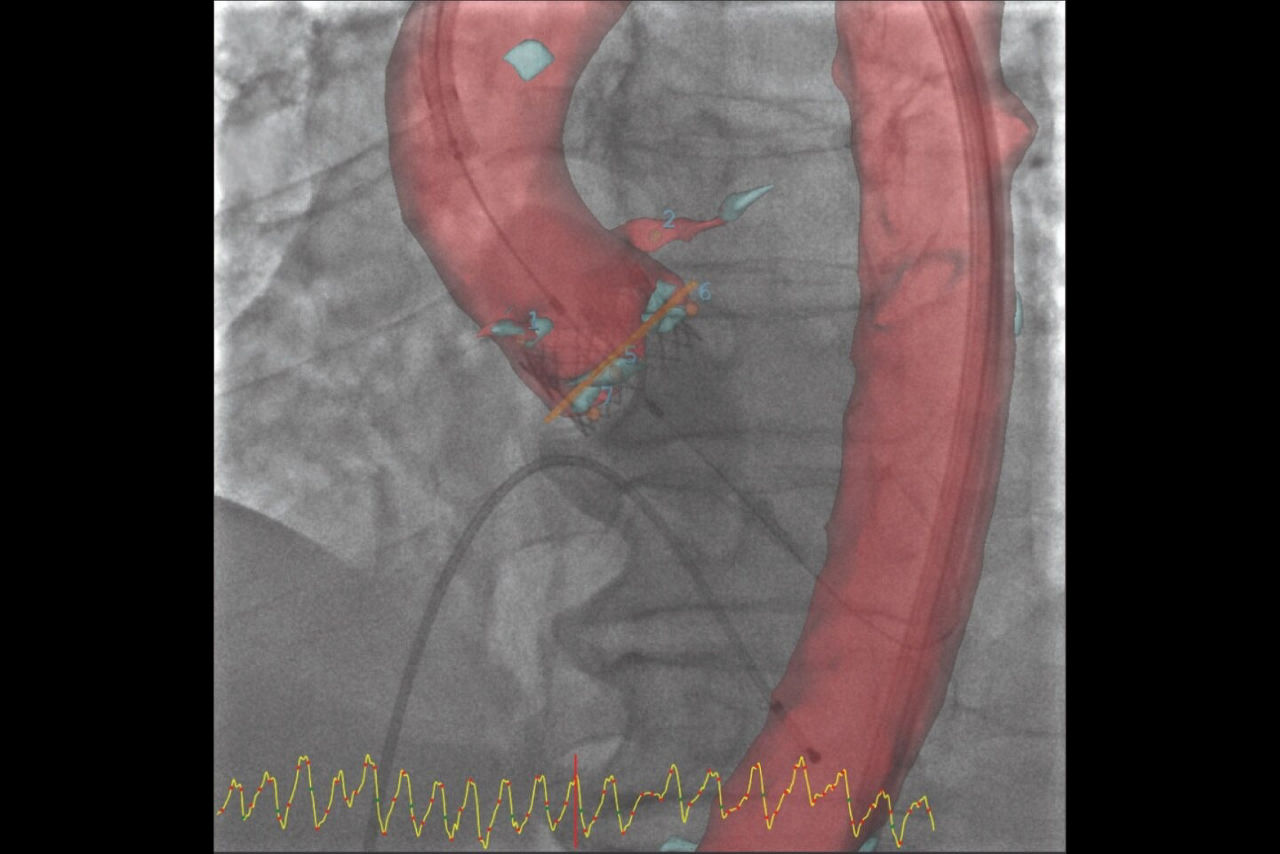

Left atrial appendage closure

Augmented guidance for more confidence with LAAC

GUIDE

3D fusion helps guide each step with confidence, from the trans-septal puncture to the device deployment. Significantly reduce procedure time, while decreasing contrast media and dose.

With Valve ASSIST 2, improve your patient outcomes in LAAC⁵:

• 78% reduction in volume of contrast media

• 28% reduction in procedure time

• 25% reduction in fluoroscopy time